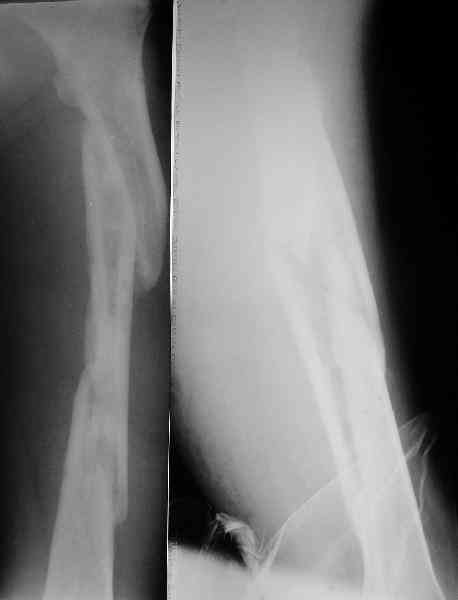

Надо делать чрескожную подвертельную остеотомию, чтобы получился открытый клин. Проблемы будут и с формированием канала, надо развертки типа наших. Был как-то похожий случай, сделали одномоментно, сняли аппарат 5-месячый на столе, заштифтовали с подвертельной остеотомией (в приложении).

Можно все коррекции сделать и в аппарате, и потом заштифтовать, тогда останется только одна проблема формирования канала.